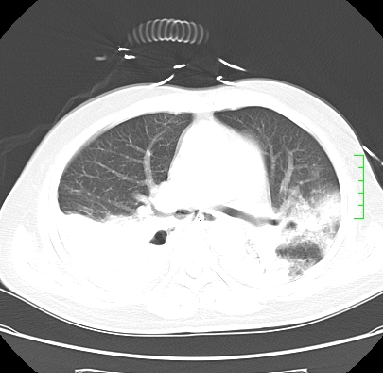

icu病人,几天都没明确诊断。m,76y,咳嗽、咳痰1周,伴气促,右胸痛入院,pe:t38.3c p135 r25 bp135/85。双肺可闻及大量湿罗音,心、腹未见明显异常。诊断:1心衰?2肺部感染?3冠心病?

双肺感染性病变,下叶膨胀不全,胸水,左室大。

1)两肺感染性病变(右肺下叶肺脓肿可能)。2)双侧胸腔积液,以右侧为甚。

混合型肺水肿合并感染,肺膨胀不全,胸膜肥厚粘连包裹,同时肺内有陈旧性病灶。注意复查

ards,肺感染性病变,右下叶实变,双侧胸腔积液,右侧为著,叶间胸膜积液,右上肺陈旧性tb纤维灶,左室大。

考虑双肺感染、右肺下叶肺脓肿伴双侧胸腔积液,肺水肿。

考虑:双肺感染、右肺下叶肺脓肿,双侧胸腔积液,肺水肿.请结合临床.